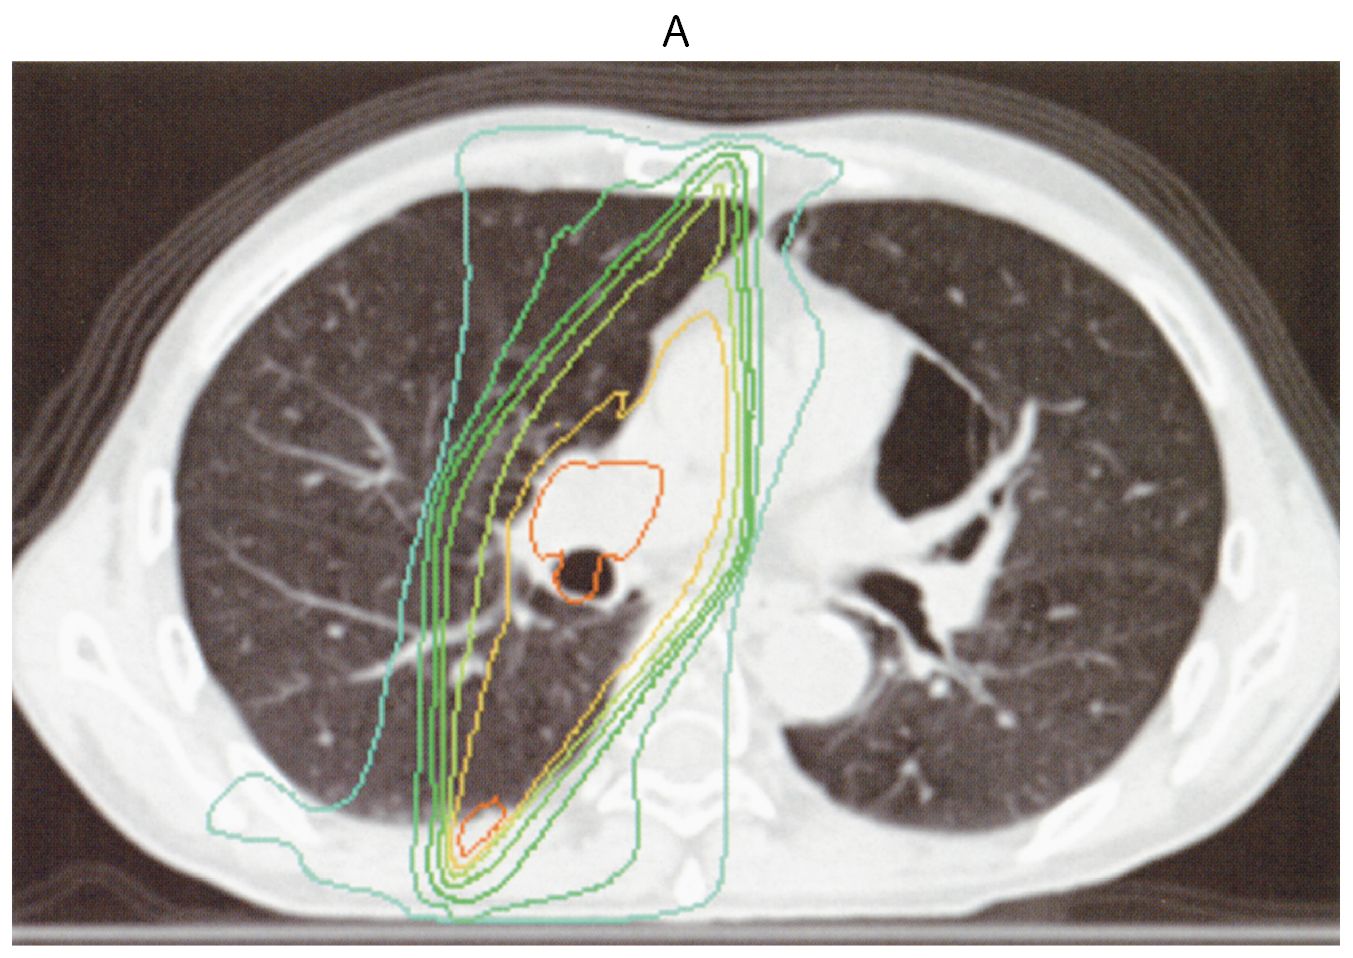

70歳の男性。1週間前からの咳と労作時の息切れを主訴に来院した。3か月前に肺小細胞癌(病期ⅢA)と診断された。診断時,自覚症状はなく,すぐに化学放射線療法が開始され,放射線治療は予定通り終了した。外来で化学療法の継続が予定されている。既往歴に特記すべきことはない。喫煙歴は30本/日を50年間。飲酒は機会飲酒。石綿などの粉塵吸入歴はない。意識は清明。身長170cm,体重62kg。体温36.5℃。呼吸数16/分。SpO2 90%(room air)。右胸部にfine cracklesを聴取する。血液所見:赤血球468万,Hb 13.9g/dL,Ht 42%,白血球7,800(分葉核好中球52%,好酸球2%,単球6%,リンパ球40%),血小板21万。血液生化学所見:LD 280U/L(基準124~222),BNP 10pg/mL(基準18.4以下)。免疫血清学所見:CRP 1.0mg/dL,β-D-グルカン2.2pg/mL(基準10以下)。胸部CT上の線量分布図(A)と受診時の胸部単純CT(B)とを下に示す。